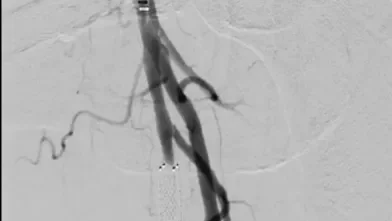

本症例は、初回治療2年後フォローアップ時のエコー所見から、DESの中枢および末梢の病変が閉塞の原因となった可能性が高い。同部位はDCBおよびDESで治療されているにもかかわらず、2年で再狭窄を呈していることから、drug technologyを用いたバルーンおよびステントでの治療は許容できないと判断した。BMI 31.9の肥満であったため右総大腿動脈より対側山越アプローチとした。6 Fr 45 cmガイディングシース + 5.5 Frシースバックアップ下に血管内超音波(IVUS)ガイドで臨んだ。エコー所見どおりDESの中枢および末梢病変は非常に強固であったため、ガイドワイヤー(40 g)で通過した。DES内の病変は非常に柔らかく、ガイドワイヤー(1 g)で通過、DCBのステント内閉塞はガイドワイヤー(15 g)を用い、IVUS下に確実に真腔内で通過した。0.014 inchガイドワイヤーの場合、ガイドワイヤーはステントストラットを容易に通過する。そのため、複数方向からの透視やIVUSを用いることで、確実にステント内を通過していることを確認することが必要となる。また、ステント内はhealthy landingではないことから、確実に前回のステントを最低1 cm以上越えて留置すべきである。DESの再狭窄は、culprit以外が柔らかい赤色血栓であることが多く、この症例もガイドワイヤーの感覚から同様の所見が疑われた。末梢塞栓予防に造影カテーテルによる可及的血栓吸引を行い、バルーン4.0 mm × 300 mmで前拡張をした。末梢病変はバイアバーン® ステントグラフト6 mm × 150 mmを留置、中枢は左浅大腿動脈起始部から10 mmのhealthy landingが残存していたため、同部位よりステントグラフト6 mm × 150 mmを留置した(図1)。高耐圧バルーン6.0 mm × 150 mmで後拡張を行い(図2、図3)、十分にgainを確保し良好なflowで終了した。治療時間は40分、造影剤使用量は70 mL であった。